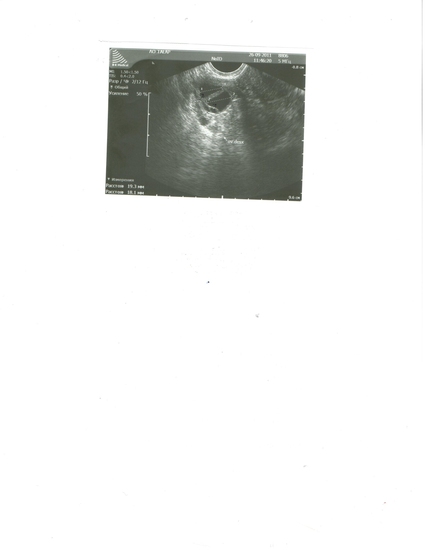

Кратко рассказываю всю неделю ныл низ живота,в суббота стал сильно болеть,уже хотела скорую вызывать и поднялась температура 37,8.В воскресенье поныл поныл и все,сейчас опять поднывает.Цикл 25-26 дней,овуляция всегда на 11-12ДЦ.На 10ДЦ был ЯБ.Но овуляцию я всегда чувствовала,а в этот раз не чувствовала вообще,единственное в червег начали груди побаливать и все.Обычно О в левом яичнике.Сегодня 15ДЦ.Итак: Матка длина 52мм передне-задний 37мм,ширина 47мм.Структура однородная,позади матки небольшое количесвто анаэхогенного содержимого.М-эхо-10мм.Цервикальный канал сомкнут,эндоцервикс 3мм.Правый яичник 41*25 с анаэхогенными образованиями 1,8см и 1,9см в диаметре.Левый яичник 36*20мм,структура неизмененна.Заключение Ки

сты желтого тела. И еще сегодня мерила БТ а она 36,2,это что значит нехватает прогестерона?